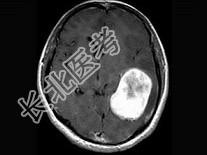

单项选择题女,34岁, 头痛数年,头颅MRI平扫及增强扫描, 最可能的诊断是 ( )

A、天幕脑膜瘤

B、星形细胞瘤

C、生殖细胞瘤

D、动脉瘤

E、三叉神经瘤